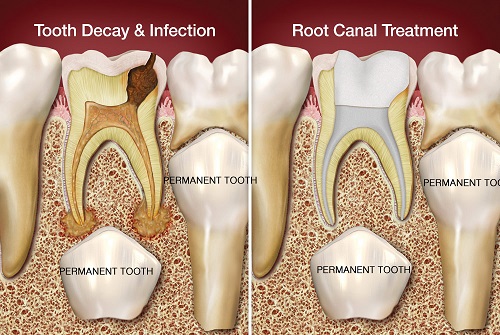

We offer microscopic root canal treatment (RCT) in order to salvage and fix a severely injured or infected tooth. Using a microscope, you receive enhanced visibility and the rapid drainage of bacteria while avoiding future suffering. We perform it under local anesthesia, so you will be comfortable most of the time.

It’s a type of root canal treatment for baby (infant) teeth. A dentist takes out any damaged pulp tissue from the pulp chamber and canals inside the tooth. If the pulp is severely damaged, the tooth is saved by cleaning and disinfecting the space and filling it with filling material.